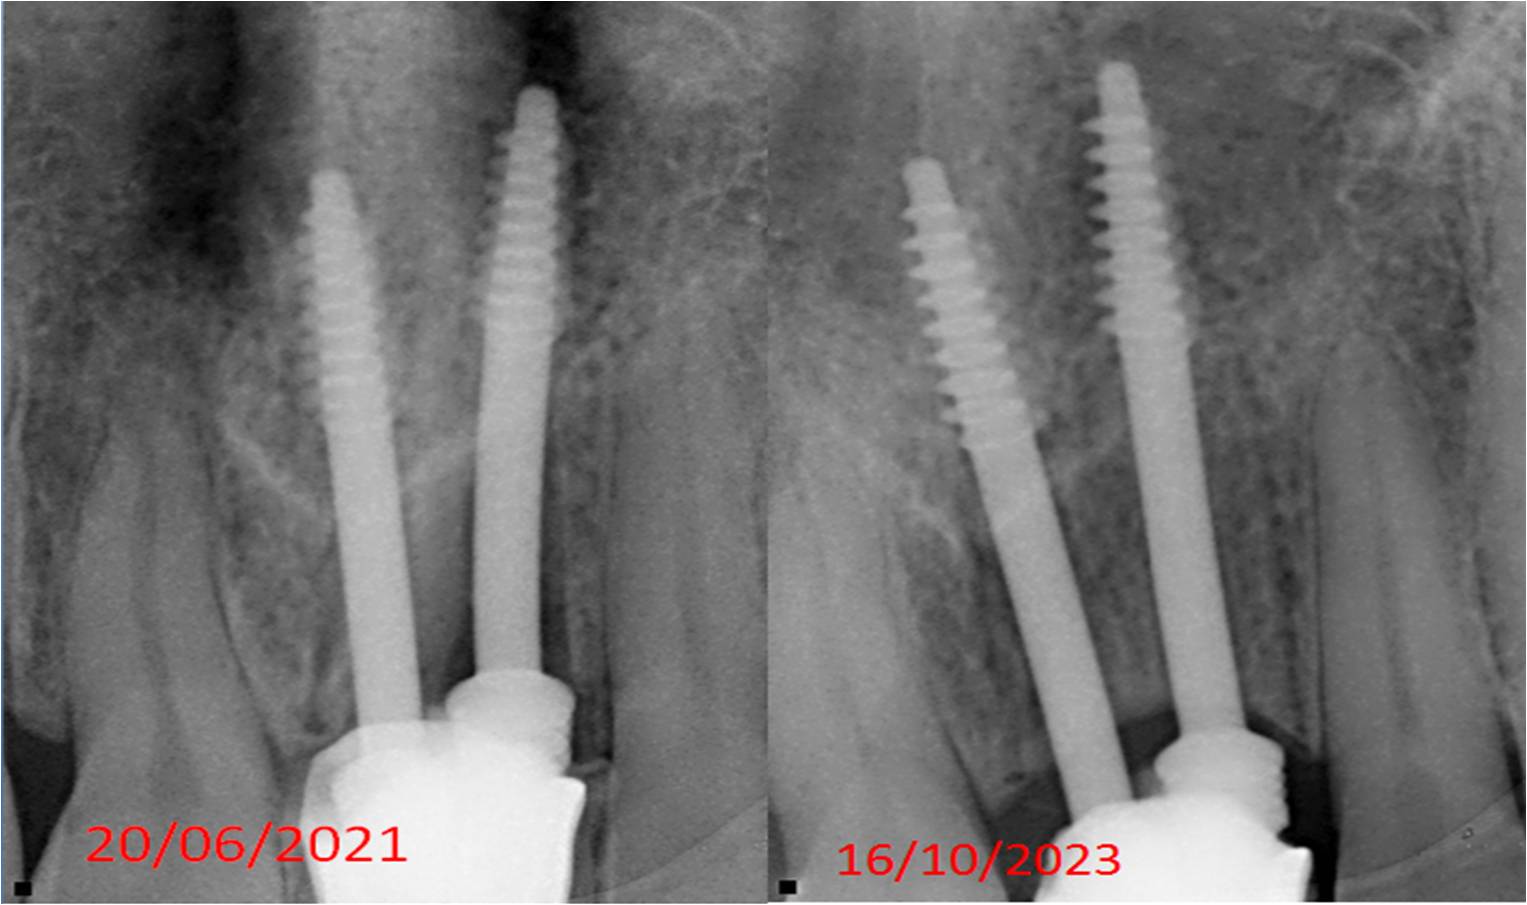

Dental Implants

We help you get a new set of teeth or a single tooth that matches your smile. Dental implants look, feel, and function like natural teeth, offering a lasting, comfortable solution.